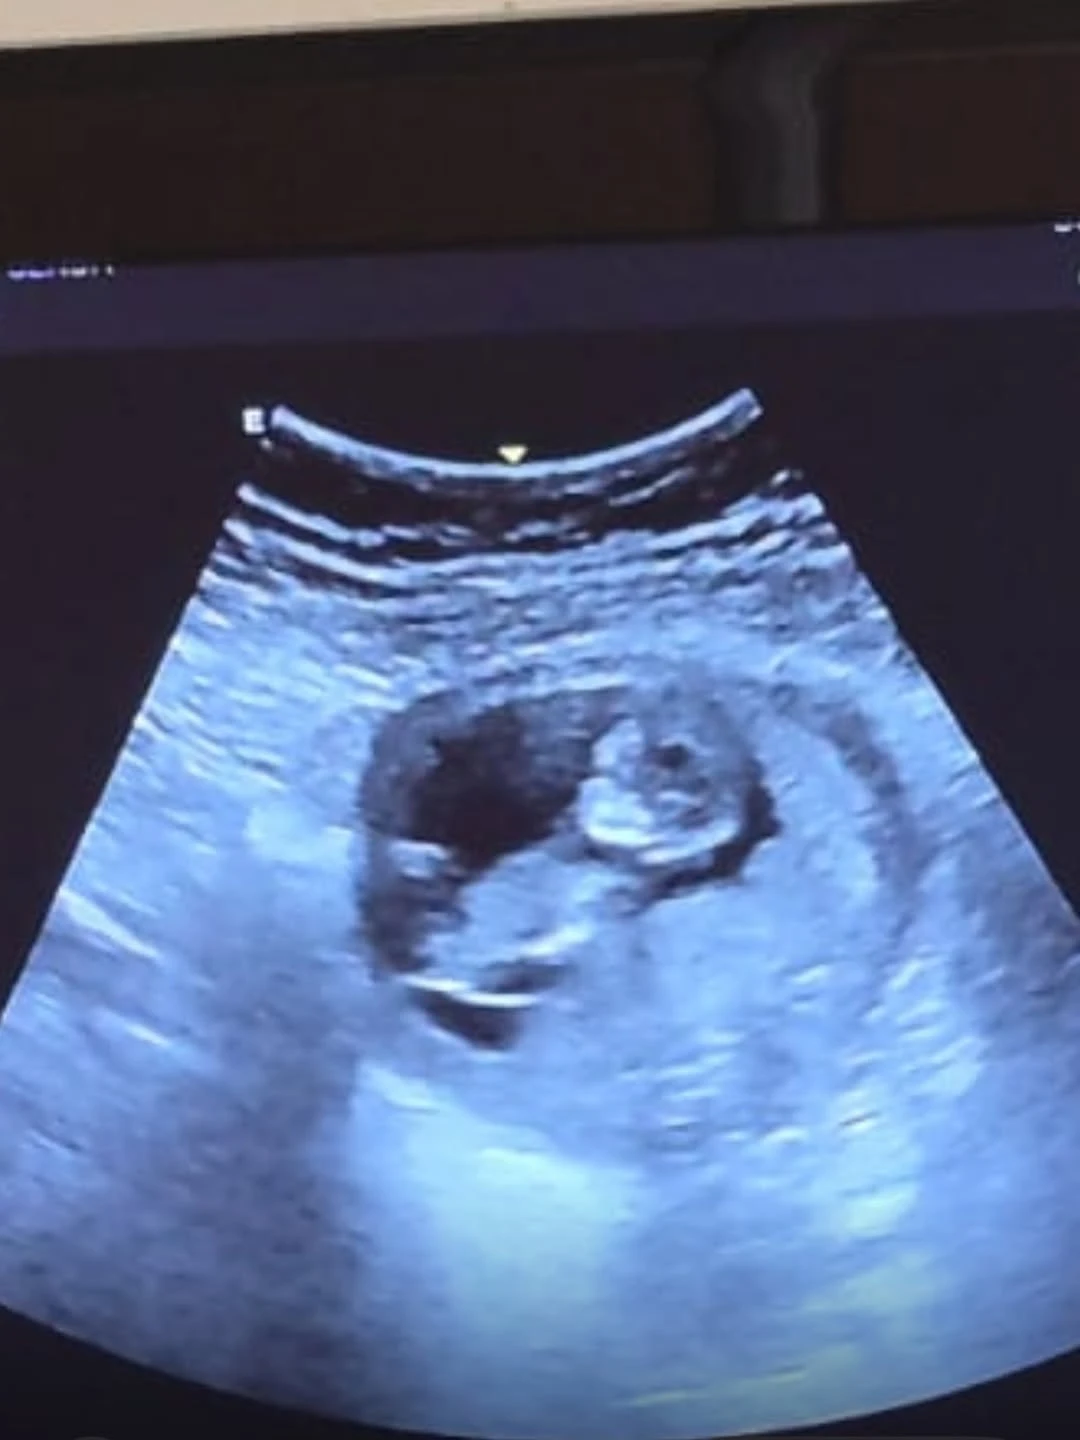

Lejos de quedar solo en el anuncio televisivo, Juli decidió compartir su felicidad también en redes sociales. A través de un carrusel de fotos en Instagram, mostró por primera vez imágenes de este proceso íntimo que transitó en silencio durante el primer trimestre.

Postales cálidas, de entrecasa y con gestos de ternura que acompañó con un mensaje simple pero contundente: “Tus papis te esperamos con mucho amor, ya te soñamos”.